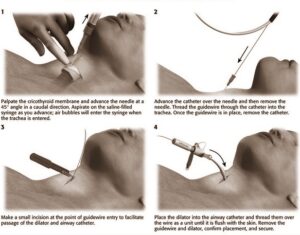

Needle cricothyrotomy in advanced life support

Indicated in case of failure to provide an airway by any other means

Complications

- Incorrect position of the cannula

- Emphysema

- Haemorrhage

- Oesophageal perforation

- Hypoventilation

- Barotrauma (change in air pressure affecting the ear or lung)